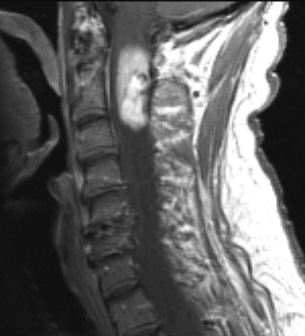

A T1-weighted image with contrast, showing marked tumor enhancement.